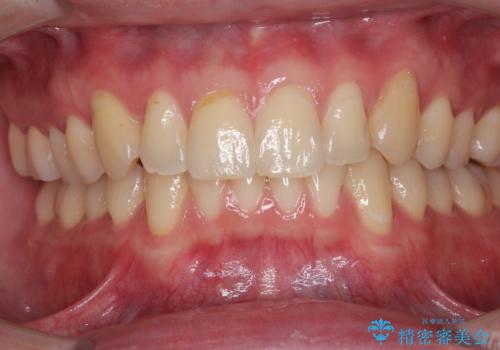

デコボコの歯とむし歯 インビザライン矯正治療とむし歯治療